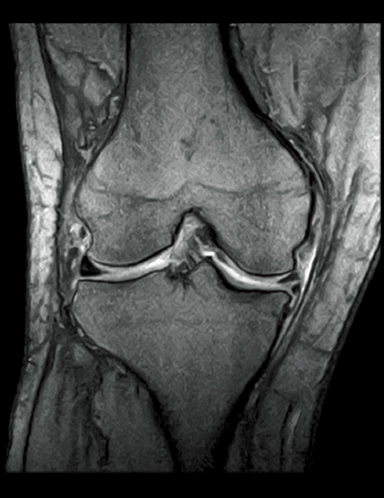

FatSat-PDWI